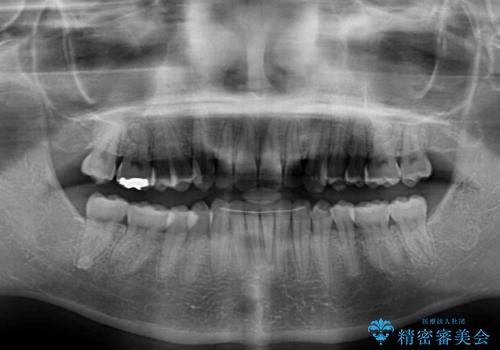

カリエール・ディスタライザーを使用している期間、反対側はワイヤー矯正により叢生を解消していくこととしました。

奥歯の咬み合わせを改善しながら、並行してインビザラインで歯列を整えることとしました。

カリエールディスタライザーやワイヤー矯正を併用したことで、確実かつ短期間で治療を終えることができました。